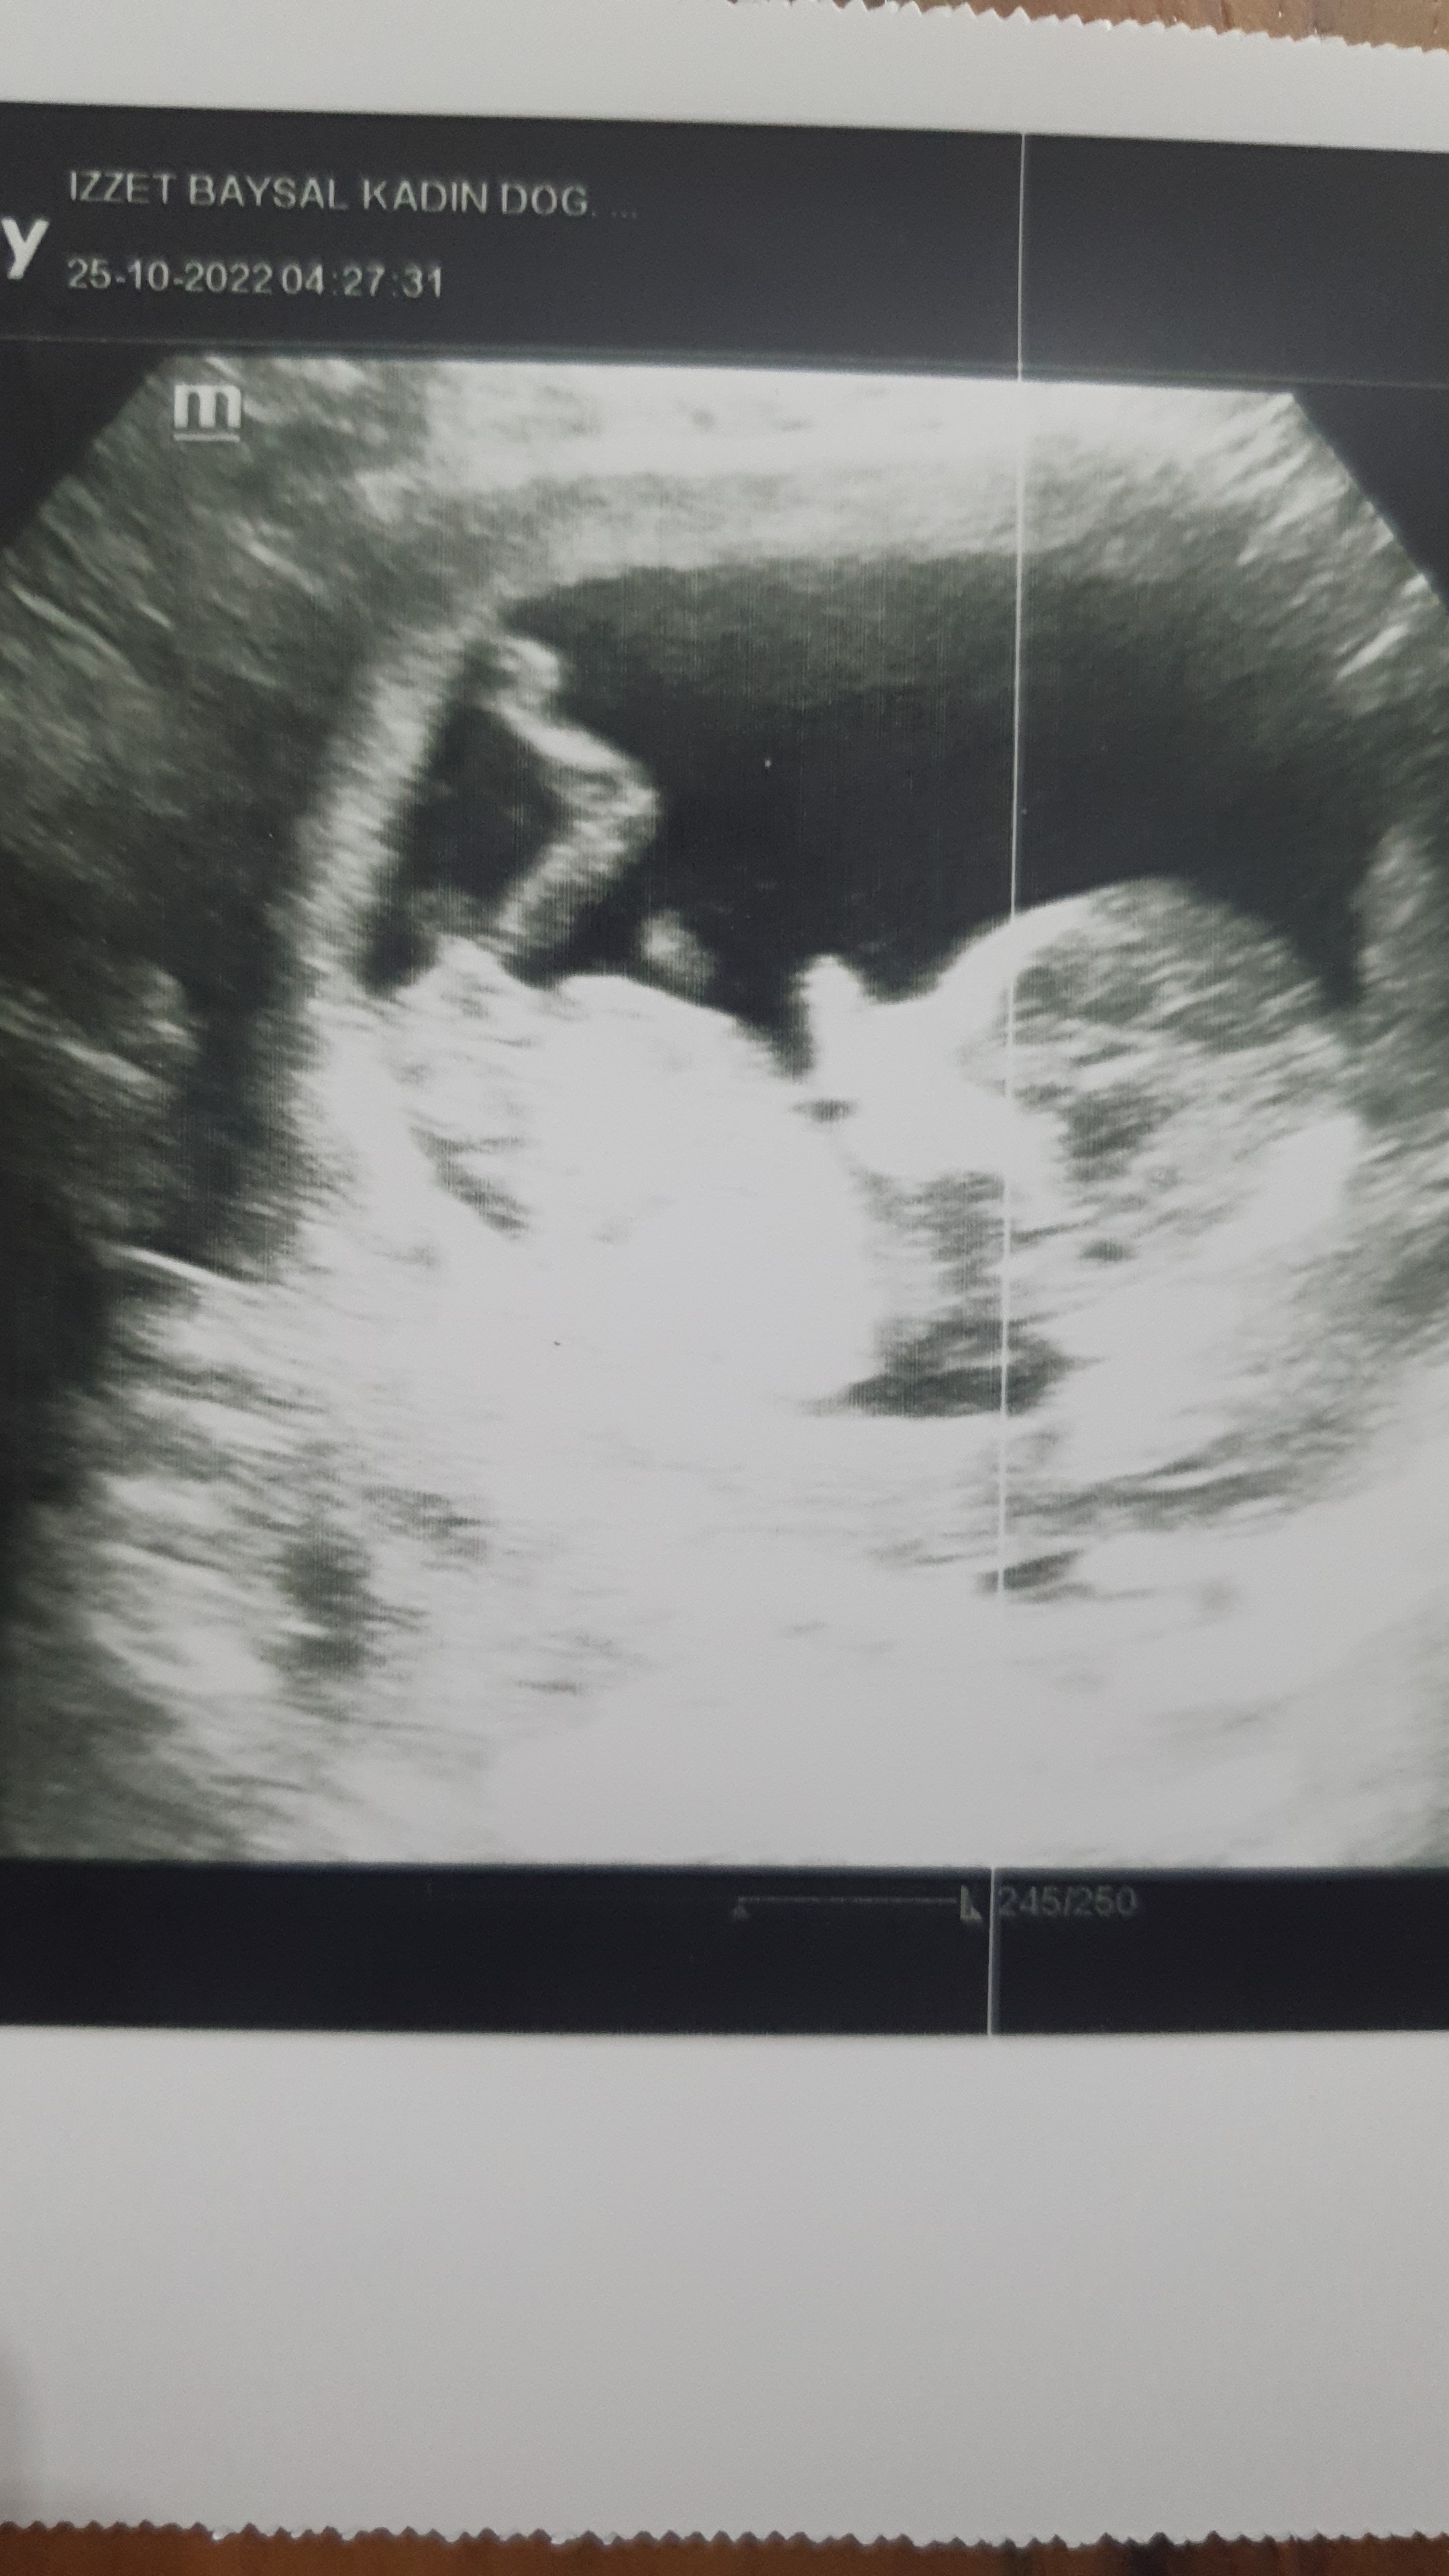

Merhabalar tekrar. Hosbuldum Resmimiz budur. Merakla bekliyorumm

Bu arada gözlerim beni yanıltmıyor ise yukarı doğru çıkıntı mevcut erkek gibi görüyorum ama çok net te değil hayatım. Tabi ki gaybı Allah bilir biz sadece bu olabilir diye söyleriz bilgin olsun 🙂 Yanılıyor olabilirim.

Tamam bi tanem Rabbim sağlıklı şekilde kucağına almayı nasip etsin. İnşallah tahminimiz doğru çıkar KIZ bi tanem öyle görüyorum 🙂